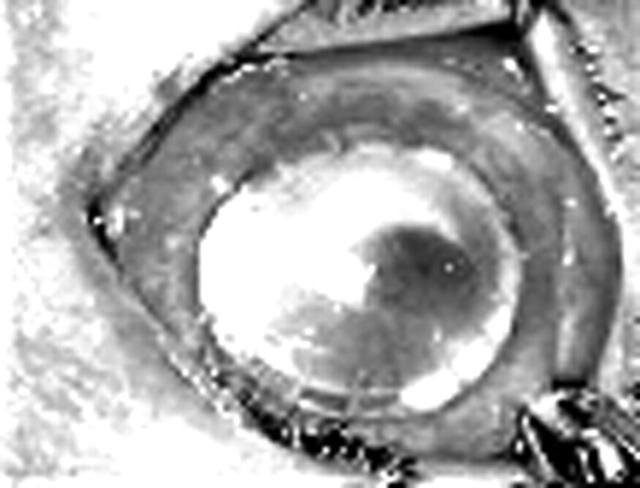

Figure 6.

Clinical photograph of case 2 showing an ulcer at the graft-host junction with hypopyon.

Figure 5.

Clinical photograph on the 10th postoperative day after therapeutic keratoplasty showing an apparently quiet eye.